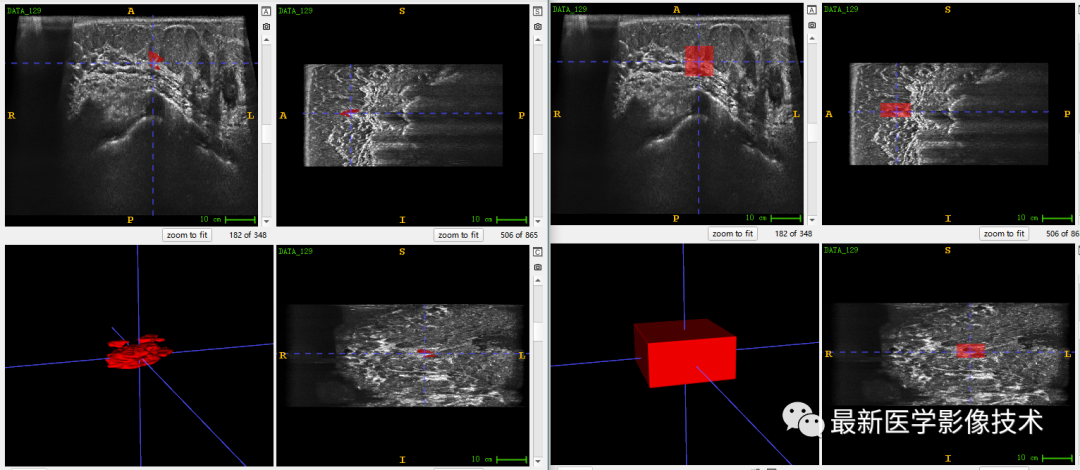

乳腺肿瘤分割采用两阶段分割网络,第一个网络进行粗分割定位肿瘤位置,第二个网络进行精分割得到肿瘤精确轮廓,然后在根据精分割mask和对应ROI图像进行良恶性分类。具体实现可以参考这篇文章TDSC-ABUS2023——2023 年自动化 3D 乳腺超声 (ABUS) 的肿瘤检测、分割和分类挑战.

验证集分割和检测部分结果如下所示。